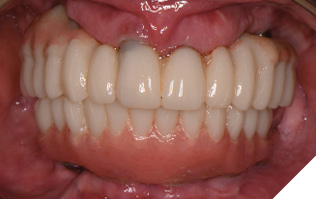

The patient returned 2 months later (due to patient scheduling delays) and the maxillary and mandibular Nexus restorations were inserted (Figs. 26A-C). Passive seating of the restorations were confirmed with the Sheffield test and radiographic confirmation. The occlusion was checked and final radiographs taken (Fig. 27).

Fig. 26A

Fig. 26B

Fig. 26C